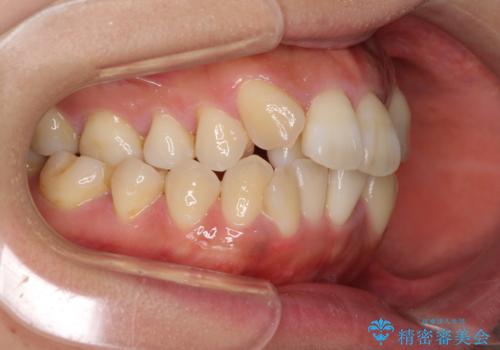

狭い上顎骨を拡大 著しい叢生を抜歯矯正で改善

- 上顎の著しい叢生と奥歯の咬みにくさを気にして来院された患者様です。

骨格的に上顎は狭く、下顎は右側にシフトしていたため、右側臼歯はクロスバイトとなっていました。

上顎骨を急速拡大装置により拡大し、ワイヤー装置による抜歯矯正治療を行うこととしました。